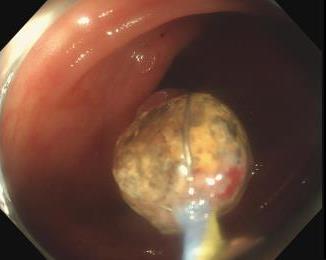

• EyeMax洞察胆胰管成像系统辅助内镜逆行阑尾炎治疗术的疗效及安全性分析

摘要:目的 探究一次性eyeMax洞察胰胆管成像系统辅助内镜逆行阑尾炎治疗术(ERAT)治疗阑尾炎的效果及安全性。方法 回顾性分析2023年4月-2024年9月在该院就诊,通过影像学或内镜检查确诊的54例非复杂性阑尾炎患者的临床资料。所有患者均行eyeMax洞察胆胰管成像系统辅助ERAT,于直视下观察阑尾腔,并通过冲洗、取石、扩张狭窄和支架引流等措施治疗阑尾炎。观察手术相关指标、术后疼痛程度、并发症发生情况、术后1年内复发率、结肠镜下表现、胰胆管成像系统下表现和胆胰管成像系统下治疗情况。结果 54例患者均顺利完成手术,技术成功率为100.0%,手术时间(60.6±27.9)min,住院时间(3.6±1.5)d;30例(55.6%)阑尾开口及周边黏膜充血水肿,2例(3.7%)可见脓液及污秽物流出;54例(100.0%)患者阑尾腔内壁充血水肿,51例(94.4%)可见腔内絮状物、脓液或脓苔附着,25例(46.3%)可见腔内粪石,15例(27.8%)可见管腔走形迂曲或狭窄。所有患者予以eyeMax洞察胰胆管成像系统治疗,简单灌洗54例,网篮取石20例,支架引流25例。术后VAS评分为0(0,0)分,明显低于术前的6(3,7)分,手术前后比较,差异有统计学意义(Z = -6.24,P = 0.000)。所有患者术后症状均暂时缓解,术中及术后未发生穿孔和大出血等严重不良事件。随访1年内,阑尾炎复发率为20.4%(11/54)。结论 EyeMax洞察胆胰管成像系统辅助ERAT是治疗非复杂性阑尾炎安全和有效的疗法,其具有直视下精准操作、保留阑尾功能、症状快速缓解、无X线暴露和精准诊疗阑尾病变等优势。值得应用于临床。